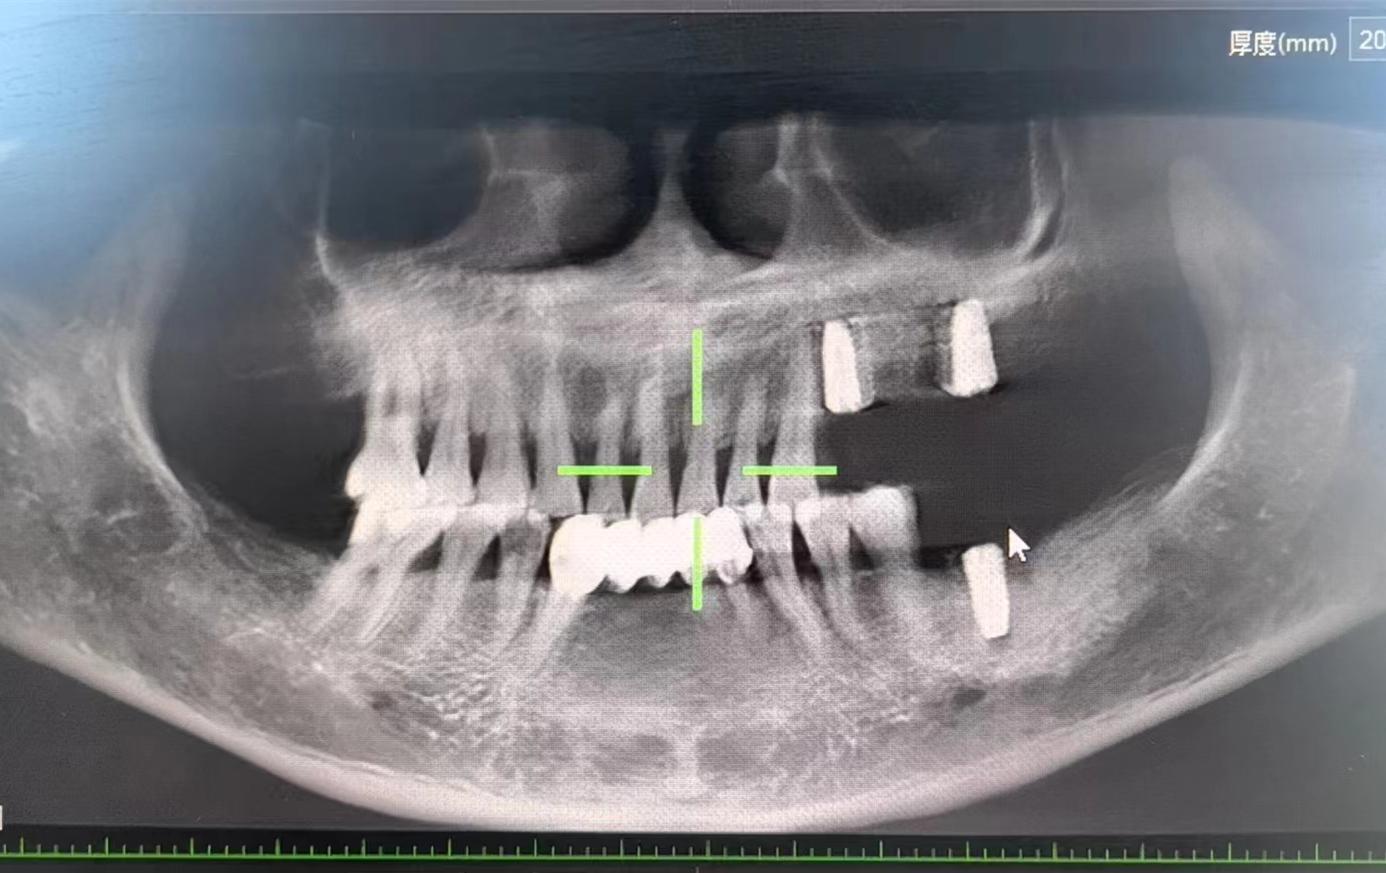

醫(yī)生檢查后,安排患者拍攝口腔CBCT,確定牙槽骨情況,并制定種植計劃,查血常規(guī),凝血功能,血壓,免疫檢查等。

為了避免患者在炎熱的夏季來回奔波,口腔科高艾玲主任團(tuán)隊決定為病人一次性種植三顆缺失的牙齒。辛璐醫(yī)生告訴患者,將通過牙科手術(shù)將人工牙根植入牙槽骨內(nèi),然后將牙齦縫合,大約10天左右拆線,之后等待骨愈合后進(jìn)行二期手術(shù)。